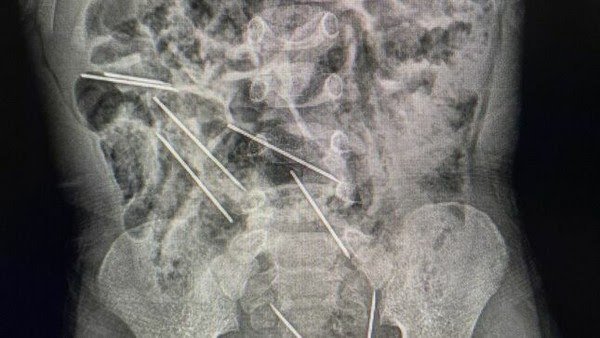

Segundo o Ministério da Saúde do país, as agulhas estavam alojadas em todo o abdômen do garoto: duas no lado direito do peritônio, três no lado esquerdo, uma na parede abdominal e outras duas entre a bexiga e o reto. A cirurgia de retirada durou aproximadamente duas horas.